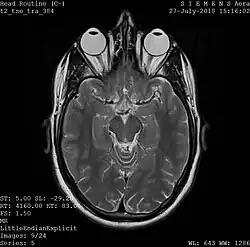

A magnetic resonance imaging instrument (MRI scanner), or "nuclear magnetic resonance (NMR) imaging" scanner as it was originally known, uses powerful magnets to polarize and excite hydrogen nuclei (i.e., single protons) of water molecules in human tissue, producing a detectable signal which is spatially encoded, resulting in images of the body.[12] The MRI machine emits a radio frequency (RF) pulse at the resonant frequency of the hydrogen atoms on water molecules. Radio frequency antennas ("RF coils") send the pulse to the area of the body to be examined. The RF pulse is absorbed by protons, causing their direction with respect to the primary magnetic field to change. When the RF pulse is turned off, the protons "relax" back to alignment with the primary magnet and emit radio-waves in the process. This radio-frequency emission from the hydrogen-atoms on water is what is detected and reconstructed into an image. The resonant frequency of a spinning magnetic dipole (of which protons are one example) is called the Larmor frequency and is determined by the strength of the main magnetic field and the chemical environment of the nuclei of interest. MRI uses three electromagnetic fields: a very strong (typically 1.5 to 3 teslas) static magnetic field to polarize the hydrogen nuclei, called the primary field; gradient fields that can be modified to vary in space and time (on the order of 1 kHz) for spatial encoding, often simply called gradients; and a spatially homogeneous radio-frequency (RF) field for manipulation of the hydrogen nuclei to produce measurable signals, collected through an RF antenna.

Like CT, MRI traditionally creates a two-dimensional image of a thin "slice" of the body and is therefore considered a tomographic imaging technique. Modern MRI instruments are capable of producing images in the form of 3D blocks, which may be considered a generalization of the single-slice, tomographic, concept. Unlike CT, MRI does not involve the use of ionizing radiation and is therefore not associated with the same health hazards. For example, because MRI has only been in use since the early 1980s, there are no known long-term effects of exposure to strong static fields (this is the subject of some debate; see 'Safety' in MRI) and therefore there is no limit to the number of scans to which an individual can be subjected, in contrast with X-ray and CT. However, there are well-identified health risks associated with tissue heating from exposure to the RF field and the presence of implanted devices in the body, such as pacemakers. These risks are strictly controlled as part of the design of the instrument and the scanning protocols used.

Because CT and MRI are sensitive to different tissue properties, the appearances of the images obtained with the two techniques differ markedly. In CT, X-rays must be blocked by some form of dense tissue to create an image, so the image quality when looking at soft tissues will be poor. In MRI, while any nucleus with a net nuclear spin can be used, the proton of the hydrogen atom remains the most widely used, especially in the clinical setting, because it is so ubiquitous and returns a large signal. This nucleus, present in water molecules, allows the excellent soft-tissue contrast achievable with MRI.[13]